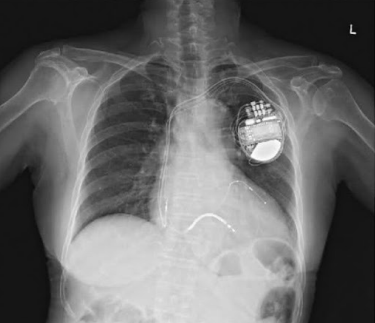

Indicações de Dispositivos Elétricos Implantáveis

- Cardiodesfibrilador Implantável (CDI): Indicado para a prevenção de morte súbita em pacientes com FEVE < 35%. O benefício é mais robusto na etiologia isquêmica comparada à não isquêmica.

- Terapia de Ressincronização Cardíaca (TRC): Indicada para pacientes selecionados que permanecem sintomáticos, em ritmo sinusal e com evidência de assincronia ventricular (ex: BRE com QRS > 120 ms).

FONTE: https://www.medicinanet.com.br/conteudos/casos/6539/marca_passo.htm